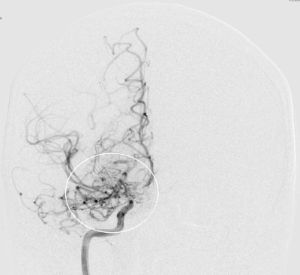

Moyamoya wurde 1957 erstmals von den Japanern Takeuchi und Shimizu beschrieben. Die Erkrankung kommt vor allem im asiatischen Raum (insbesondere Japan und Korea) häufiger vor, wobei man von einem Auftreten (Inzidenz) von ca. 0.35/100.000 Einwohnern/Jahr ausgegangen wird. Für den europäischen Raum gibt es bis heute keine verlässlichen Daten, jedoch schätzt man, dass die Erkrankung hier ca. 10x seltener als oben genannt vorkommt. Der Name „Moyamoya“ stammt aus dem Japanischen und bedeutet übersetzt „Rauchwolke“, was auf das diffuse Erscheinungsbild feiner Kollateralgefäße in der Gefäßdarstellung „Angiographie“ zurückzuführen ist.

Die Krankheit tritt nur im Bereich der basalen Hirnarterien auf und dehnt sich nicht weiter auf die peripheren Hirngefäße aus. Da das Großhirn sechs Hauptversorgungsgebiete hat (jeweils beidseits eine vordere, eine mittlere und eine hintere Hirnarterie), können bei einer betroffenen Person bis zu 6 Gefäßterritorien betroffen sein. Welche Hirnareale definitiv beteiligt sind, kann man erst sicher nach der Durchführung einer Angiographie (Katheterdarstellung der Hirngefäße) sagen.

Die konventionelle cerebrale Angiographie ist die wichtigste Untersuchung zur Diagnosestellung der Moyamoya Krankheit. Diese Untersuchung ist zu vergleichen mit einer Herzkatheteruntersuchung, eben nur mit Darstellung der Hirnarterien. Bei Moyamoya-Patientinnen und Patienten werden, im Gegensatz zu Routineuntersuchungen bei anderen cerebralen Erkrankungen, selektiv die vordere und hintere Zirkulation des Gehirns dargestellt, sowie auch die Versorgung der extrakranialen Gefäße. Diese umfassende Darstellung ist besonders wichtig, um die vollständige Ausdehnung der Erkrankung zu erfassen und alle möglicherweise veränderten Blutflüsse im Gehirn zu verstehen. Je nach Befund werden die Engstellen der Hirnarterien, sowie auch mögliche begleitende Veränderungen selektiv hochauflösend dreidimensional dargestellt. Es ist wichtig zu erwähnen, dass die Moyamoya Krankheit nicht über eine Katheterintervention (Ballonaufweitung der Engstelle) behandelt werden kann und darf. Dies haben mehrere Studien gezeigt.

Angiographie beidseitige Moyamoya Krankheit

Konventionelle Angiographie eines Patienten mit beidseitiger Moyamoya Krankheit (links). 3-dimensionale Darstellung eines Aneurysmas einer jahrelang stark beanspruchten Spontan-Kollaterale (rechts).